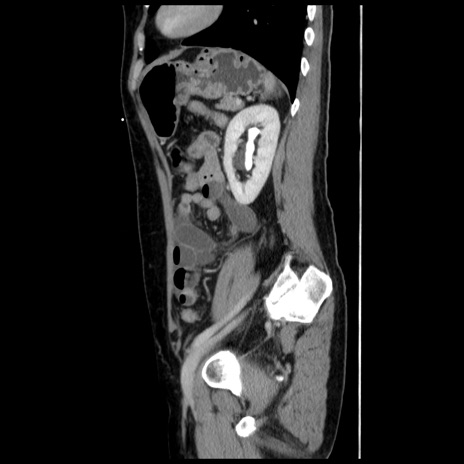

症例10(矢状断像)

【症例】 50歳代女性

【主訴】 腹痛

【現病歴】前日生レバーを食べた。今朝に排便あり。 昼前に突然発症の腹痛を生じ、当院救急外来を受診した。

【既往歴】 子宮筋腫にてで子宮全摘後

【身体所見】 意識清明、腹部:平坦、軟、下腹部やや左を中心に圧痛・反跳痛あり、筋性防御あり

【データ】WBC 7800、CRP 0.07